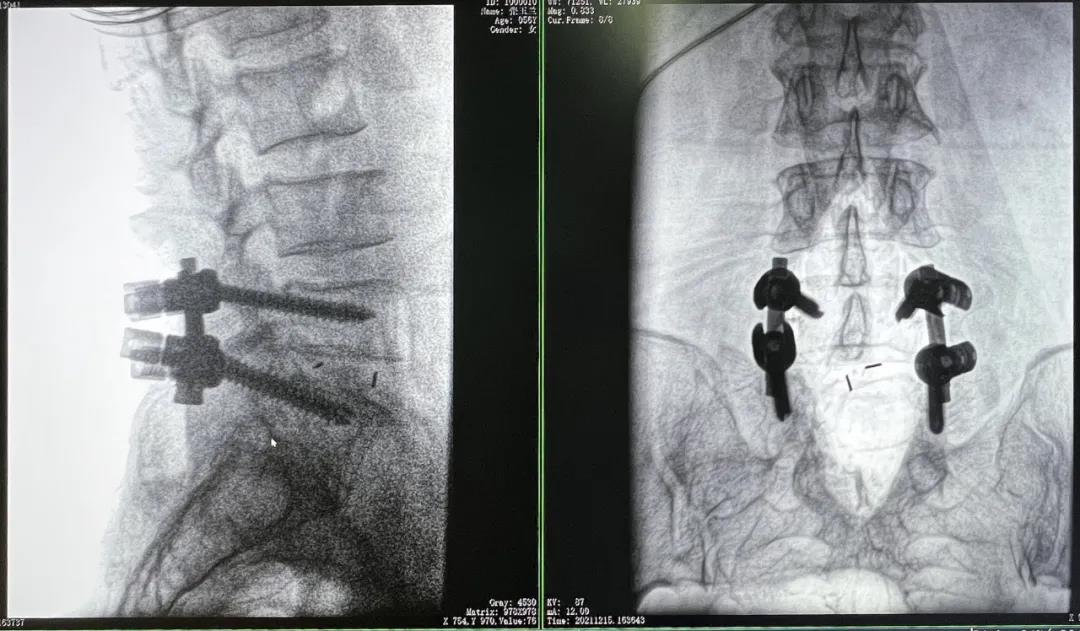

3D C形臂摆位及手术前二维影像

医生在影像引导下在L5/S1椎弓根处打入医用螺钉